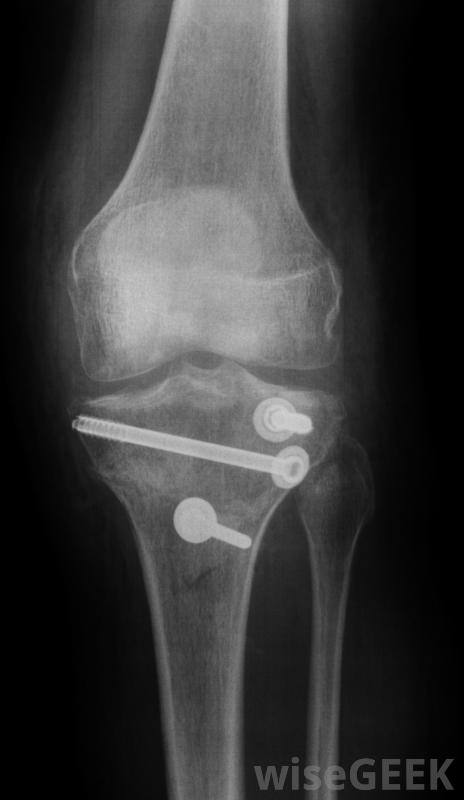

骨科手术设备可能包括塑料剪和外科凿子。骨夹和骨科锉刀是骨科手术中使用的另外两种设备。其他类型的骨科手术设备是骨锉和骨规。钉植入物用于固定骨段。

在骨科手术中,许多手术都需要植入金属棒和金属针。在这种手术中,外科医生需要测量针、螺丝钉、螺丝钉的精确长度,一种用于切割这些金属针的金属丝的矫形外科手术设备是一种外科针刀。这些切割机由不锈钢制成,拥有非常强大的下颚。

拧紧将杆和销固定在骨头上的螺钉。这些螺钉也可用于在手术过程中取下螺钉。这些手术钳的手柄设计成防滑的,在外科医生的手上很舒服。